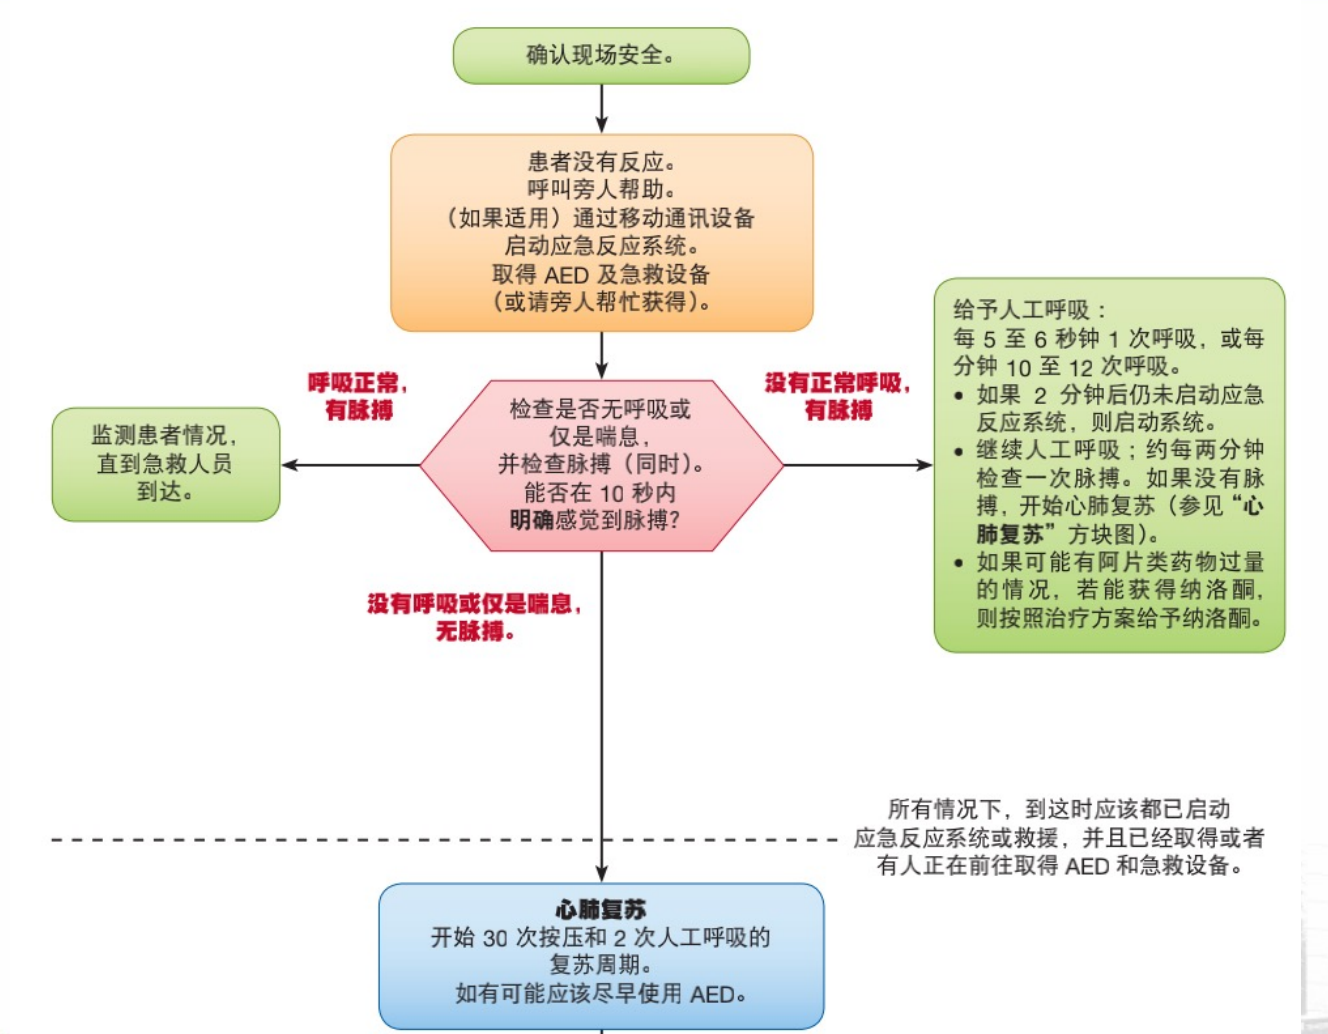

成人基础生命支持(BLS):

- 判断环境

- 判断患者的意识

- 一旦患者无意识,应立即启动紧急医疗系统(EMS)

- 判断呼吸和脉搏

C-A-B:按压(Compression)、气道(Airway)、呼吸(Breathing)

口对口/鼻 人工呼吸:连续吹2口气,缓慢吹气,每次持续>1秒

总结:

AED——自动体外除颤器: